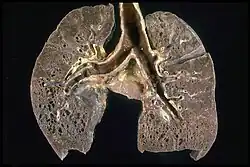

Respiratory tract

Localization to the lungs is by far the most common manifestation of sarcoidosis.[27] At least 90% of those affected experience lung involvement.[28] Overall, about 50% develop permanent pulmonary abnormalities, and 5 to 15% have progressive fibrosis of the lung parenchyma. Sarcoidosis of the lung is primarily an interstitial lung disease in which the inflammatory process involves the alveoli, small bronchi, and small blood vessels.[29] In acute and subacute cases, physical examination usually reveals dry crackles.[28] At least 5% of cases include pulmonary arterial hypertension.[28][30] The upper respiratory tract (including the larynx, pharynx, and sinuses) may be affected, which occurs in between 5 and 10% of cases.[31]

The four stages of pulmonary involvement are based on radiological stage of the disease, which is helpful in prognosis:[32]

- Stage I: bilateral hilar lymphadenopathy (BHL) alone

- Stage II: BHL with pulmonary infiltrates

- Stage III: pulmonary infiltrates without BHL

- Stage IV: fibrosis